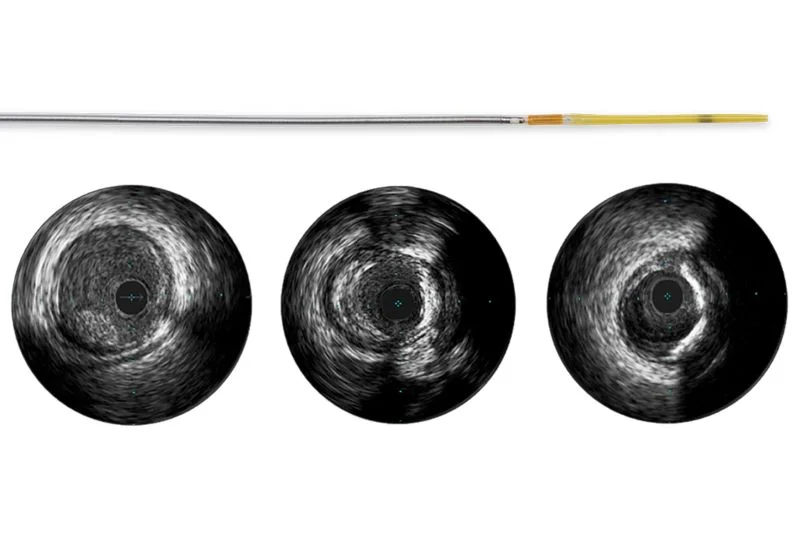

ВСУЗИ оборудование

Philips Volcano

Полная линейка для внутрисосудистой визуализации и физиологии: катетеры Eagle Eye Platinum, ротационный Refinity 45 МГц, проводник давления OmniWire, платформа IntraSight и ПО SyncVision.

ВСУЗИ показывает поперечное сечение артерии в реальном времени — размер сосуда, состав бляшки, степень стеноза. Ангиография даёт лишь силуэт.

Визуализация

Миниатюрный датчик создаёт 360° ультразвуковое изображение стенки сосуда изнутри